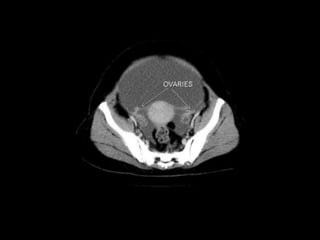

Pelvic peritoneal space

The pelvic peritoneal space is the inferior reflection

of the peritoneum over the fundus of the urinary bladder and the front of

the rectum at the junction of its middle and lower thirds. In females, the

reflection is also over the anterior and posterior surface of the uterus and

the upper posterior vagina.In males there is only one potential space for fluid collection posterior to

the bladder, the rectovesical pouch.

In females there are two potential spaces posterior to the bladder,

the uterovesical pouch, and posterior to the uterus the

deeper rectouterine pouch (pouch of Douglas).

The layers of peritoneum on the anterior and posterior surfaces of the

uterus are reflected laterally to the pelvic side walls as the broad ligaments,

containing thefallopian tubes.